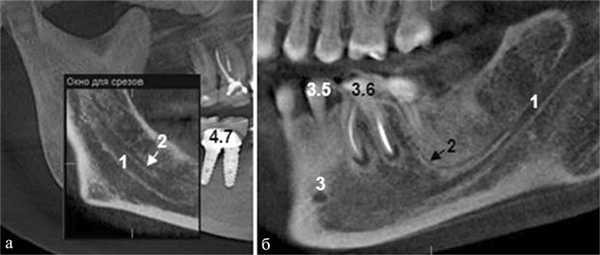

Пациентка Ф., 55 лет. С правой стороны на уровне угла челюсти от верхней стенки нижнечелюстного канала начинался дополнительный канал с поперечным диаметром 1,52 мм (рис. 3, а). Рис. 3. Дентальный канал нижней челюсти. а — КЛКТ пациентки Ф., 55 лет; б — КЛКТ пациентки К., 29 лет. 1 — канал НЧ; 2 — дентальный канал; 3 — подбородочное отверстие. Поперечный диаметр основного канала на этом же уровне — 2,70 мм. Дополнительный канал направлялся полого вперед и вниз параллельно основному каналу НЧ. В мезиальном направлении кортикализация стенок дополнительного канала постепенно уменьшалась, и достоверно проследить его ход удалось до уровня зуба 4.7. Описанная картина характерна для дентального канала (3-й тип раздвоенного канала НЧ). С левой стороны визуализация дополнительного канала была недостоверной: выявлялось линейное просветление такой же локализации и направления, как с правой стороны, но картины трубчатого образования не выявлено, вероятнее всего — вследствие недостаточной кортикализации его стенок.

У пациентки К., 29 лет, с левой стороны обнаружен дентальный канал (см. рис. 3, б). В месте отхождения он имел вертикальный диаметр 1,35 мм (приблизительно в 3 раза меньше вертикального диаметра канала НЧ на этом же уровне), направлялся вперед и вниз, располагаясь параллельно основному нижнечелюстному каналу, и на уровне медиального корня зуба 3.7 круто поднимался вверх. Дентальный канал переставал идентифицироваться на уровне средней трети корня второго нижнего левого моляра. С правой стороны раздвоения канала НЧ не выявлено.

Пациентка Б., 57 лет. С правой стороны на уровне угла НЧ определялась добавочная ветвь нижнечелюстного канала диаметром 1,1 мм, которая, начинаясь от его верхнего контура, далее шла вперед почти параллельно основному каналу на протяжении 8,01 мм, а затем сливалась с ним (рис. 5). Рис. 5. Конфигурация канала НЧ; КЛКТ пациентки Б., 57 лет. 1 — канал НЧ; 2 — передний канал. На контралатеральной стороне добавочных каналов не обнаружено. Описанная рентгенологическая картина соответствует 1-му (а) типу раздвоенного канала НЧ.